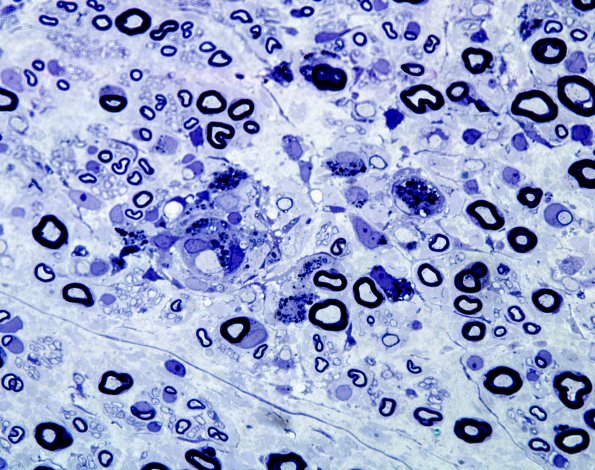

Washington University Experience | PERIPHERAL NEUROPATHY | 7A GUILLAIN-BARRE SYNDROME (GBS) | 7A5 GBS (Case 7) Plastic 2 best

There are many regions in which the number of demyelinated and thinly remyelinated axons are markedly increased. (Plastic sections)